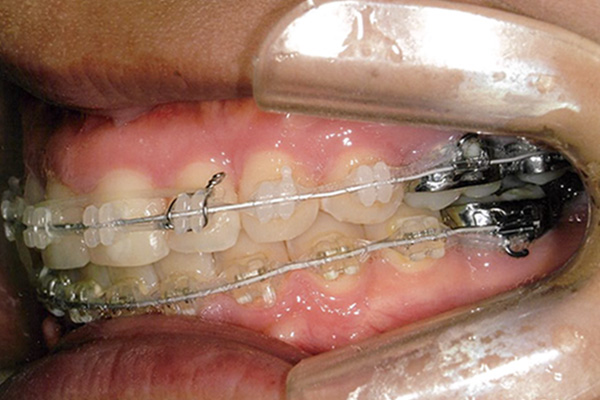

| 症状 | 下顎第一大臼歯の欠損 |

| 想定されるデメリット | 臼歯の近心移動が非常に難しい。高度なテクニックが必要である。 3D-LST矯正治療法を用い、抜歯を最小限に抑えながら歯の近心移動を実施。 |